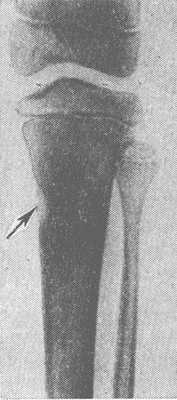

Рис. 1. Рентгенограмма голени: видна Лоозера зона в корковом слое большеберцовой кости в виде полоски просветления, имитирующей неполный перелом (указана стрелкой).

Рентгенол, симптоматика Л. з. весьма характерна, в особенности при локализации Л. з. в трубчатой кости. Сначала на рентгенограмме появляется едва заметная полоска просветления в диафизе с ровными контурами, пересекающая его в поперечном направлении. Крайне редко эта полоска может иметь косой или зигзагообразный ход. Вначале она может быть видна на одной стороне кости, создавая картину, сходную с неполным переломом (рис. 1), а в дальнейшем может распространяться уже на весь поперечник диафиза. К этому времени появляются более или менее обширные периостальные наслоения с обызвествлением, внешне аналогичные периостальной костной мозоли. Нередко на фоне периостальных наслоений полоска просветления едва прослеживается. Такая картина возникает часто в репаративном периоде заболевания. На отдельных этапах развития Л. з. могут возникать затруднения в диагностическом толковании рентгенол, картины, поскольку она формально может иметь сходство не только с переломом, но и с саркомой или корковым абсцессом кости (рис. 2). В целях дифференцирования особое значение приобретают повторные исследования.